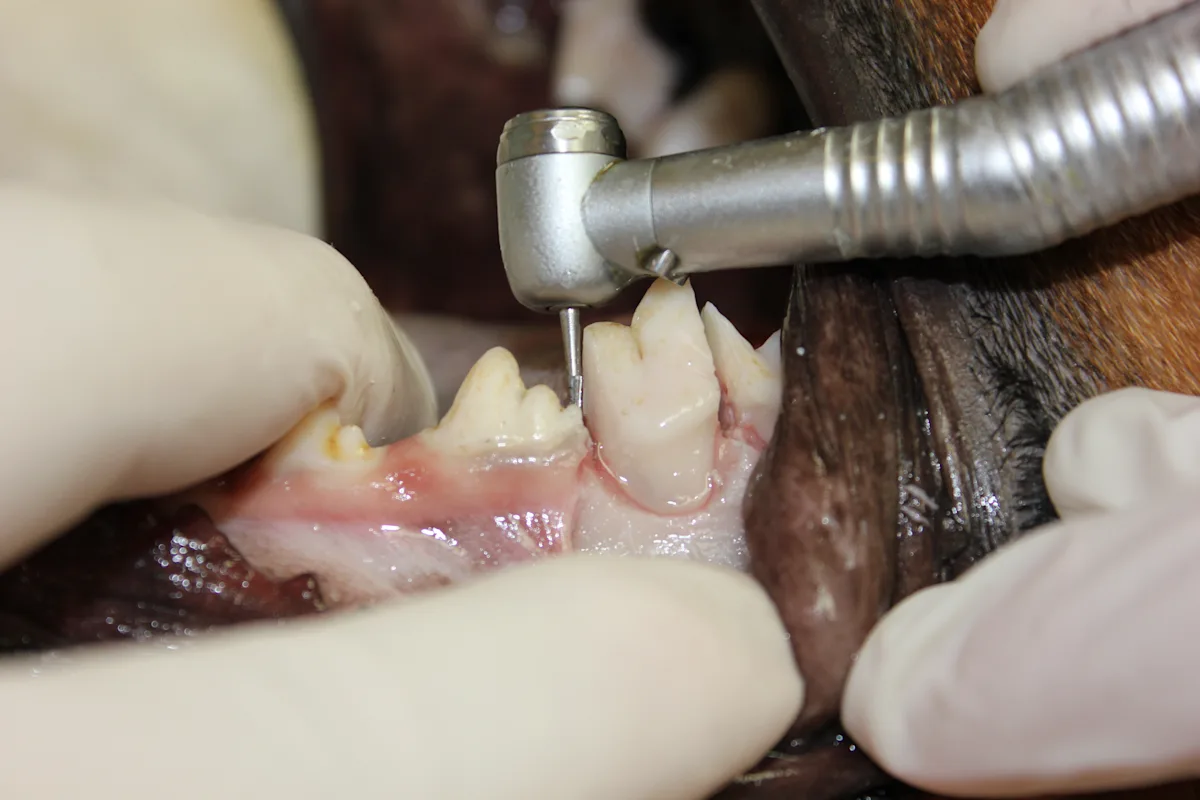

Use a #8 round bur in a water-cooled high-speed handpiece with light pressure to remove the alveolar bone and expose the furcation.

Round burs range in size from #2 to #8, increasing in size with the number. Bur size is selected based on the size of the patient.